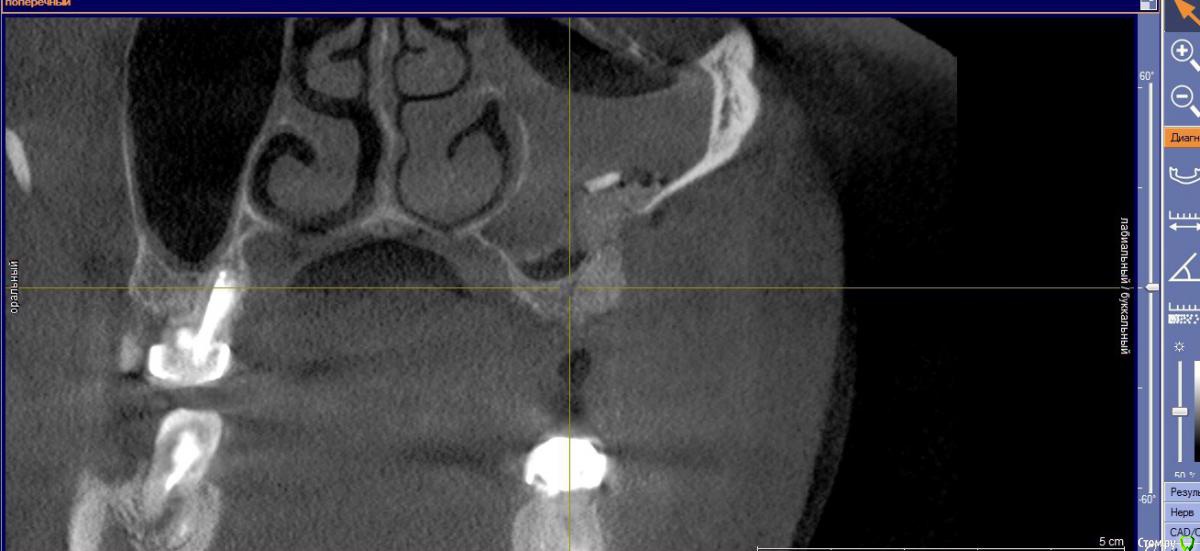

Bier Опубликовано 27 августа, 2016 Поделиться Опубликовано 27 августа, 2016 В пазухе отек, а вот кость придется добавлятьА что за инородное тело на 3м снимке? Ссылка на комментарий

Fibez Опубликовано 27 августа, 2016 Поделиться Опубликовано 27 августа, 2016 Бир, похоже на кусок кортикалки. Ссылка на комментарий

Кариес+ Опубликовано 27 августа, 2016 Автор Поделиться Опубликовано 27 августа, 2016 Да это кортикалка , оттек может быть связак с моим вмешательством? Это может быть кровь или физ.раствор от пьезотома? Если предположить что я прорвал синус Ссылка на комментарий